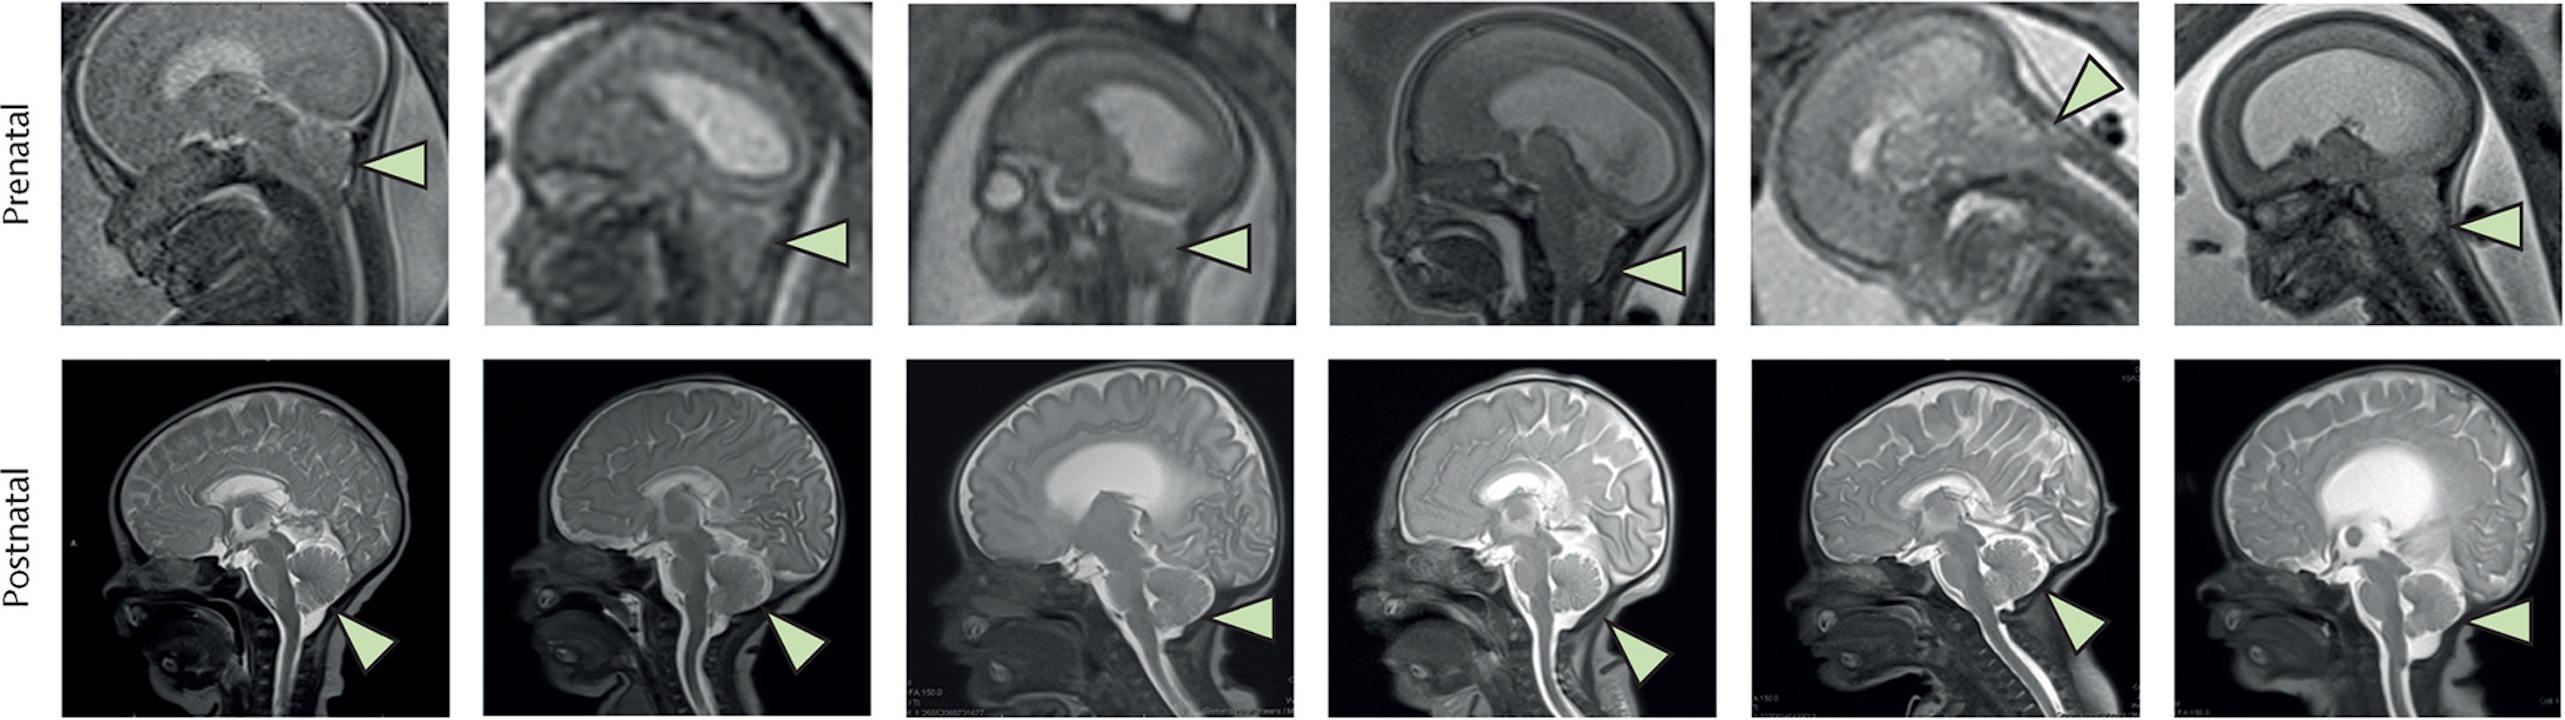

Завдяки лікуванню в дітей зникла грижа (позначена трикутником) в районі з'єднання спинного та головного мозку (верхній ряд — знімки до терапії, нижній — після народження). Farmer et al. / The Lancet, 2026

У дослідженні взяли участь шість вагітних, у чиїх дітей в утробі діагностували розщеплення хребта. Усі немовлята народилися у 2021-2022 роках шляхом кесаревого розтину без ускладнень, слідів інфекції, патологічного росту тканин або утворення пухлин. Магнітно-резонансна томографія після народження також підтвердила відсутність у них гриж у районі з’єднання спинного та головного мозку, які є частим наслідком розщеплення хребта та спостерігалися в дітей ще в утробі. Для оцінки ефективності такого лікування в порівнянні зі звичайною операцією планують провести наступний етап клінічного випробування за участі вже 35 пацієнтів.